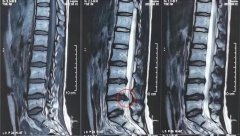

不到30岁就腰椎间盘突出了! 当代年轻人的身体状况哪里出了差错?

最近一则很有意思的短视频 讲的是当代年轻人的身体状况 内容大概如下: 你的长辈在健身器材上锻炼 上下翻飞,身体倍棒 你的晚辈在操场上,欢快跳操朝气十足 而20、30岁的年轻人猛